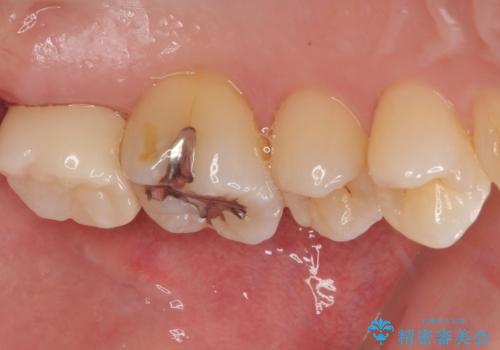

- 元々むし歯があったものの、処置が困難とのことでしたが、矯正治療を終えたので処置をしたいとのことで来院された患者様です。

左右ともに最後臼歯が頬側に顕著に突出しており、むし歯になってしまったことが想像されました。

矯正治療により処置が可能な位置に歯が移動したため、オールセラミッククラウンにて補綴治療を行うこととしました。

歯列が移動したとはいえ、左右ともに後方傾斜しており、むし歯の除去、形成(形を整える)、型取りの全てが非常に困難な処置となりました。